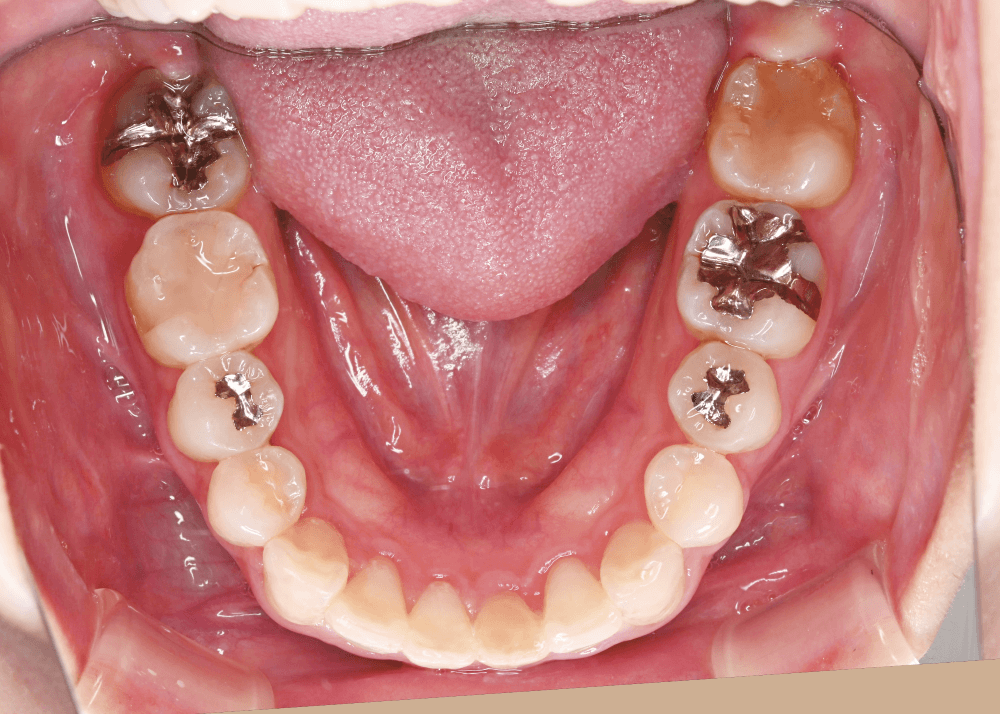

治療前の状態

すでに矯正治療を終えられていたため、歯列に大きなガタつきはなく、上下の歯の咬み合わせも良好でした。

しかし顔貌の観察では以下の特徴が見られました。

側貌(横顔)

上顎前歯が舌側に強く傾斜しており、口唇のサポートが不足していました。

その結果、口元のボリュームが少なく、横顔がやや平坦な印象となっていました。

スマイル時の印象

患者様ご本人も

「笑ったときに歯が奥まって見える」

という違和感を強く感じておられました。

歯並び自体は整っていても、前歯の位置や傾斜によって口元の印象は大きく変化します。